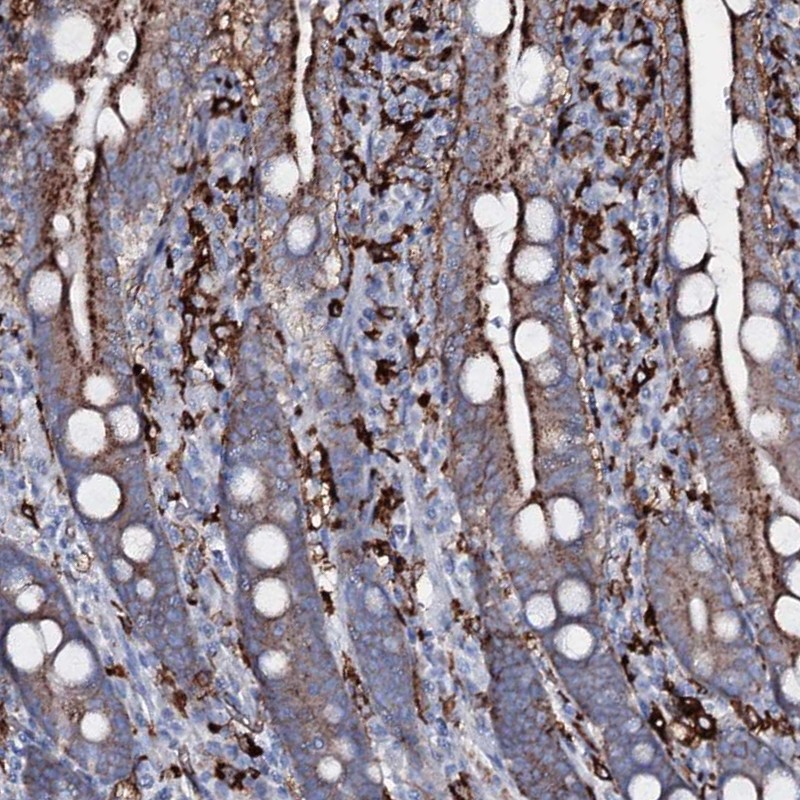

Immunohistochemical staining of human duodenum shows cytoplasmic positivity in glandular cells.